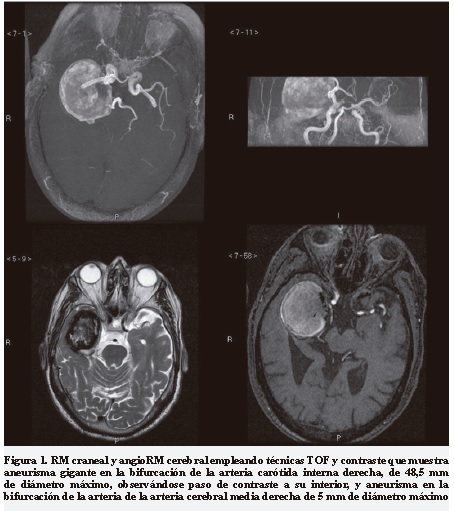

Paciente de 68 años con antecedentes de osteoporosis. Hace diez años comenzó con episodios de desconexión breves precedidos en ocasiones de cuadro compatible con déjà vu en frecuencia variable. De forma esporádica seguían con pérdida total de conciencia, caída al suelo y contracciones tónico-clónicas en los cuatro miembros. La resonancia magnética nuclear con angiorresonancia mostró un aneurisma gigante intracraneal en la bifurcación de la arteria carótida interna derecha, de 48,5 mm de diámetro máximo junto a otro de 5 mm de diámetro máximo en arteria cerebral media derecha. El aneurisma gigante se encuentra en proximidad de la bifurcación de la arteria cerebral media derecha y de la arteria cerebral posterior derecha (Figura 1).

La exploración neurológica es normal; el hemograma, bioquímica de rutina, no muestra hallazgos significativos y los niveles farmacológicos se mantienen en rango. El electroencefalograma muestra un foco irritativo temporal derecho congruente con la localización de las dilataciones aneurismáticas. La resonancia magnética se muestra en la Figura 1.